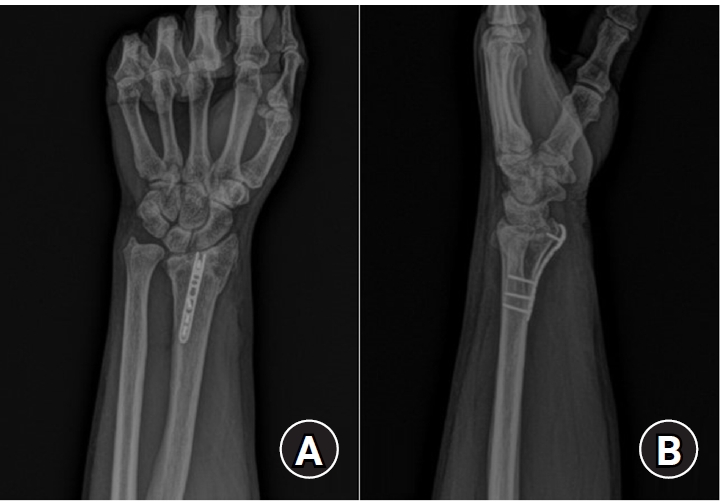

Fig. 3.

Postoperative radiographs (anteroposterior and lateral). (A) Volar articular marginal fragment of the distal radius fixed by two plates: a standard 2.4 mm LCP-L distal radius plate (Synthes) and a 2.0 mm locking compression plate distal ulnar hook plate (Synthes). (B) Additional percutaneous pinning after plating. (C) Additional percutaneous pinning and external fixator after plating.

Fig. 3. Postoperative radiographs (anteroposterior and lateral). (A) Volar articular marginal fragment of the distal radius fixed by two plates: a standard 2.4 mm LCP-L distal radius plate (Synthes) and a 2.0 mm locking compression plate distal ulnar hook plate (Synthes). (B) Additional percutaneous pinning after plating. (C) Additional percutaneous pinning and external fixator after plating.